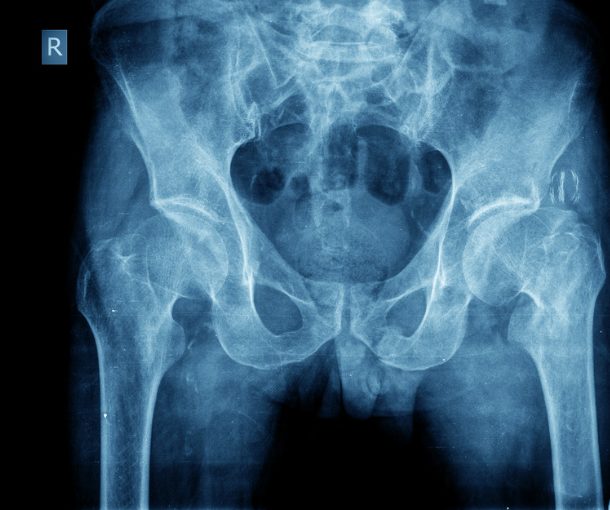

大腿骨頸部骨折は上の二つと同様骨粗しょう症を背景に転倒がきっかけで生じることが多い骨折です。

股関節痛が強く動けない方もいれば、骨折部が噛み込んで安定し歩いて来院する方もいます。

基本的に体重をかけるとズレが大きくなり、骨がつきにくくなるので、よっぽどのことがない限り手術をすることが多いです。

そのため早期診断が大切になります。

診断はレントゲンで行います。

レントゲンはわかりにくい場合もあるため、その時はCTを確認します。

治療は基本的には手術です。

骨を金属の固定具で支え、骨を温存し骨癒合をさせる手術、骨を完全に人工物・金属で置き換える手術、人工股関節に置き換える手術など手術方法は患者さまの背景や骨折のタイプによってえらばれます。